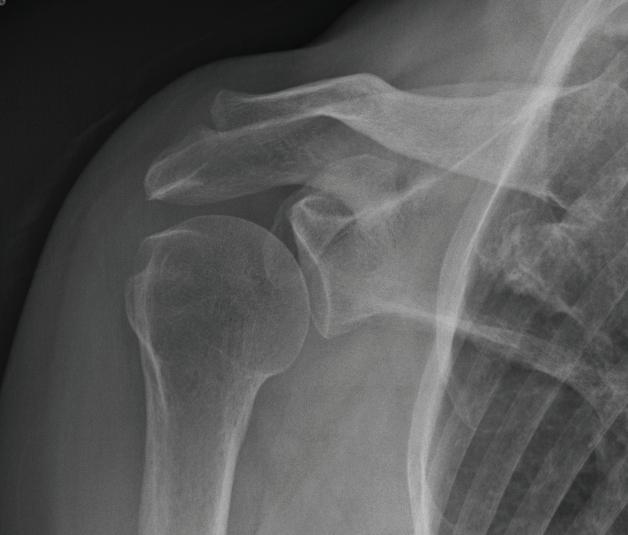

Figure 1-6 is an example of a common posterior oblique projection of the shoulder, described by Grashey

FIGURE 1-6 Grashey (oblique shoulder) view radiograph (top) and a schematic drawing of patient orientation for the Grashey view (bottom).

in 1923, used for ideal visualization of the glenohumeral joint.

In Figure 1-6, the patient is rotated to his right in relation to the x-ray beam. The most important issue when viewing oblique images is that there is no uncertainty about which anatomic structures are on the right side of the patient and which are on the left side. In other words, if an oblique projection of the cervical spine clearly reveals cervical neuroforamina, the important issue is that there must be certainty as to whether these are the right or left neuroforamina. It does not matter if the oblique view was done as a right posterior oblique or a left anterior oblique, as long as an “R” marker indicates to the viewer which side of the image is the right side of the patient or an “L” marker indicates the left side of the patient.